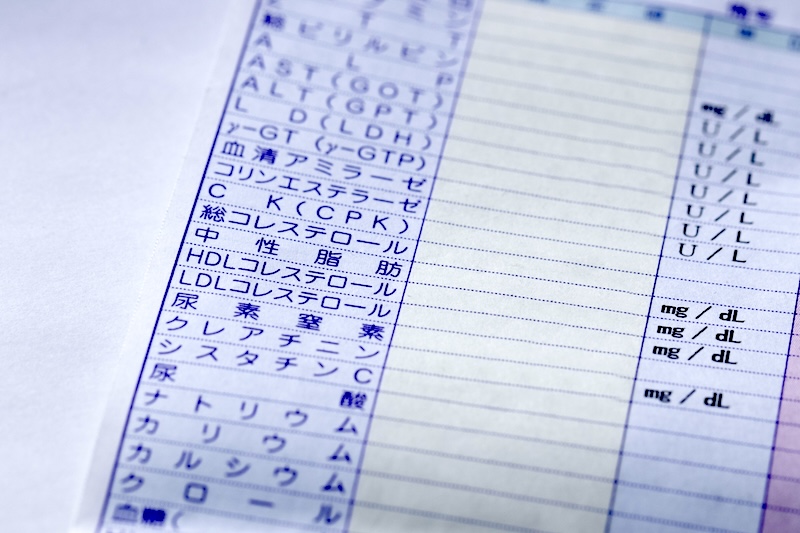

健康診断前の食事は何時間前まで?8時間? 10時間?

健康診断前は何時間食事を空けるべきかを、中性脂肪・血糖などの影響や前日の飲酒・運動の注意点とあわせてまとめました